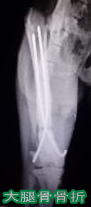

整形外科治療セット

小川病院 ; 完備   南台病院 ; 完備

パワードリル、マイクロエンジンをはじめ

骨折(プレートやピンの内固定)や脱臼、椎間板ヘルニアなど

の手術に必要な整形外科器械器具を各種取り揃えております。

※ レントゲン写真は当院での治療例です。

当院での整形外科手術による2023年9月時点の治癒率

(通常の歩行ができるようになった)は以下の通りです。

・骨折95%以上(2009年以降は100%)

・前十字靭帯断裂、膝蓋骨内方脱臼、股関節脱臼それぞれ100%

※この記載は治癒を保証するものではありません。